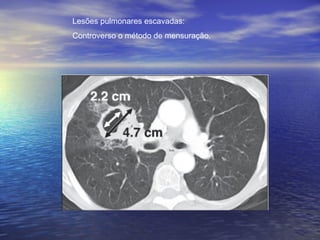

Lesões pulmonares escavadas:

Controverso o método de mensuração.